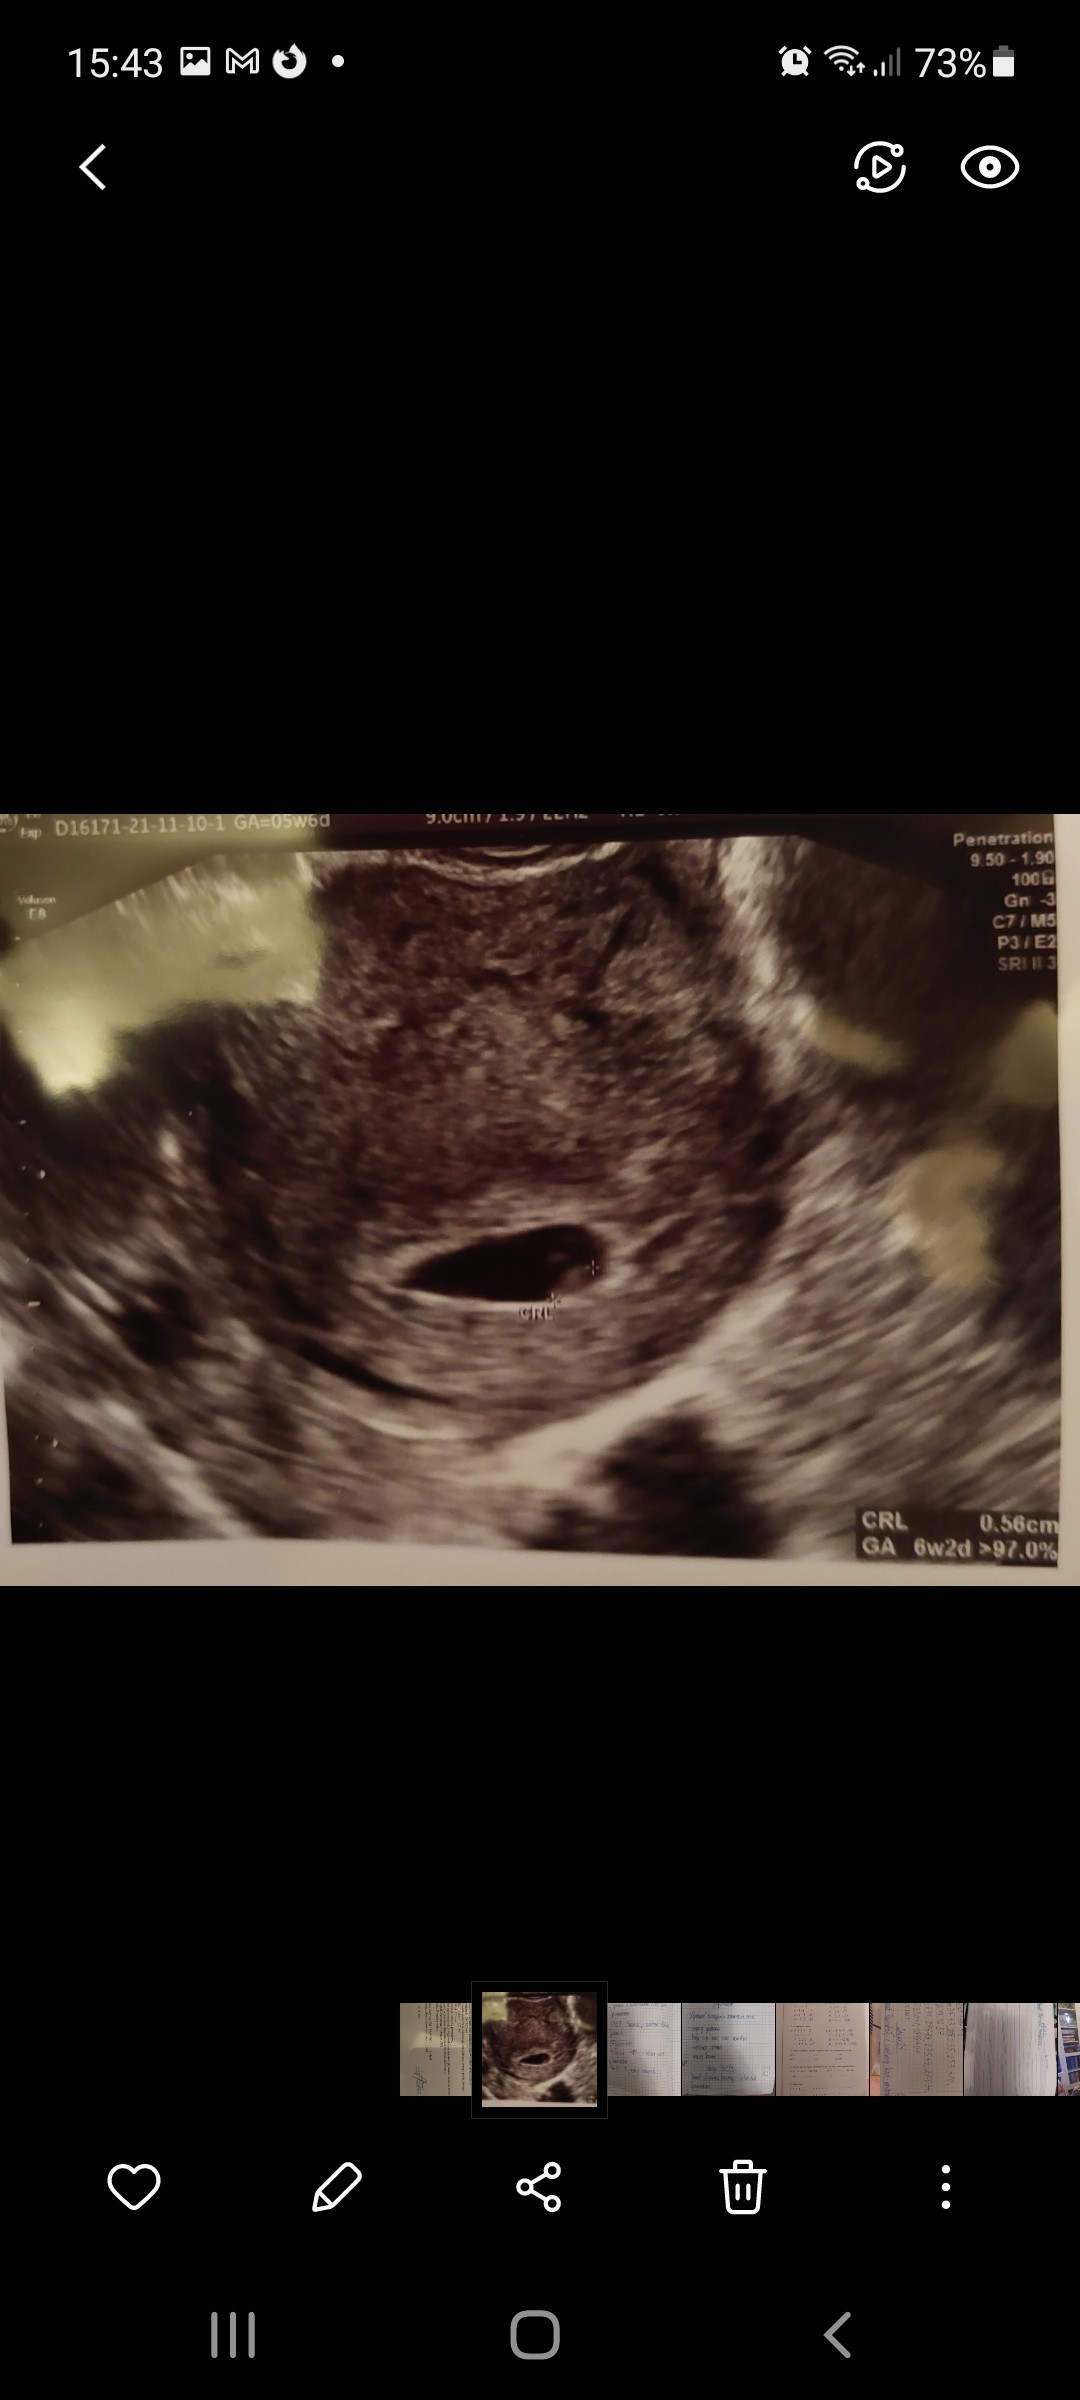

Jestem po wizycie u mojego ginekologa. Efekty w załaczeniu na foto.

Mój lekarz powiedział, że powinnam prowadzić ciążę u Pani profesor która jest ordynatorem na oddziale patatologii ciąży bo ona ma zdecydowanie większe doświadczenie w prowadzeniu ciąż wysokiego ryzyka.

Moją nazwał ciążą bardzo wysokiego ryzyka. Mam na koncie niedoczynność tarczycy, cukrzycę ciążową, 2 obumarcia, grupę RH minus (mąż ma plus), skończone 40 lat, ciąże donoszone też były z "przygodami".

Pęcherzyk wg niego jest nieco spłaszczony. Powiedział że mam leżeć i zwiększyć dawkę luteiny na 2x200 dopochwowo. Oprócz tego Fraxiparine 0.4 raz dziennie, Acard150 przed snem, witaminy, kwas foliowy, magnez, probiotyk dopochwowo.

Także zapisałam się na wizytę do tej Pani profesor za dwa tygodnie, bo wcześniej nie było dostępnych terminów.

Martwi mnie ten kształt pęcherzyka. Oczywiście czarno to wszystko w tej chwili widzę.